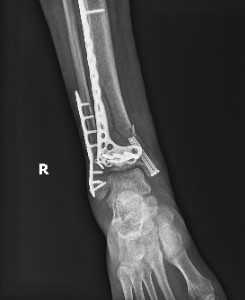

Status post ORIF with plate and screws in the distal fibula and tibia with 2 screws in the medial malleolus. A portion of the fracture line is still evident in the tibia.

Radiographs and CT scan confirmed healing fractures with a congruent mortise, but hardware impingement on dorsiflexion and eversion.

Status post ORIF with plate and screws in the distal fibula and distal tibia with healed fracture of the distal shaft of the tibia with mild deformity with anatomic alignment maintained.Healed fracture of the distal fibula without residual deformity.

Healed medial malleolus fracture without deformity.